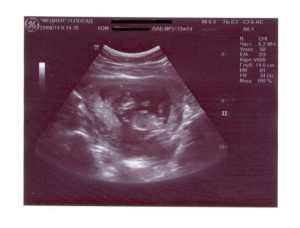

Если женщина не проводила ультразвуковое исследование плода на более ранних сроках, то УЗИ на 12 неделе беременности становится первым и приобретает особое значение.

Срок уже позволяет маме разглядеть малыша целиком, пусть пока и на мониторе оборудования. А доктор имеет возможность оценить анатомические особенности плода и рассказать о них будущей матери.

С медицинской точки зрения, УЗИ-скрининг 12 недель (1 триместра) представляет немалую ценность для определения мероприятий по дальнейшему ведению беременности и сохранению здоровья малыша.

Современное ультразвуковое исследование позволяет будущей маме наблюдать за происходящим на экране ультразвукового аппарата наряду с доктором. И первое обследование становится первой встречей мамы с сыном (или дочкой).

Справка! Хотя на мониторе ещё сложно разглядеть ребёнка в привычном понимании, женщины с волнением ждут этого момента.

Самое главное на данном этапе – убедиться, что всё идёт так, как должно. И, конечно, когда врач говорит: “Послушайте, как бьётся сердечко ребёнка. Вот голова, вот ножки, а вот ручки, все пальчики уже сформировались. Всё у вас хорошо”, – мама испытывает прилив счастья.

К 12 неделям беременности все органы ребёнка и системы его организма полностью сформированы.

Справка! Вес малыша сейчас – не больше 19 граммов, а длина тельца – около 9 см.

Нередко на УЗИ женщина видит, как малыш сосёт пальчик, причём его ноготки уже сформированы. Хаотичные движения крохи продуманы природой – во время них он тренирует свой мышечный аппарат.